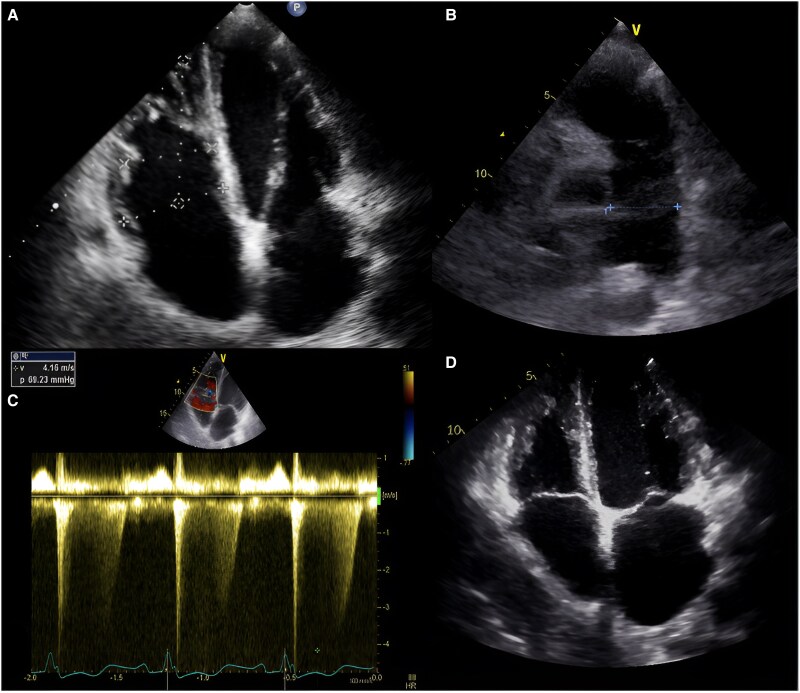

Case report: A 33-year-old male with a long-standing, progressively enlarging AVM of the right upper limb presented with necrosis and haemorrhage, leading to hypovolemic shock. Angiography revealed an AVM involving the subclavian, axillary, and brachial arteries, necessitating embolization and surgical interventions. Six years later, he developed distal finger necrosis, requiring infracondylar amputation. He later presented with stump infection, purulent discharge, orthopnoea, jugular venous distension, a loud second heart sound, and a holosystolic murmur in the tricuspid region. Echocardiography and catheterization confirmed PAH and a high-flow arteriovenous fistula. Multidisciplinary evaluation led to definitive amputation and PAH treatment. Postoperatively, PAH resolved, and the patient was discharged with ongoing follow-up, showing significant improvement.